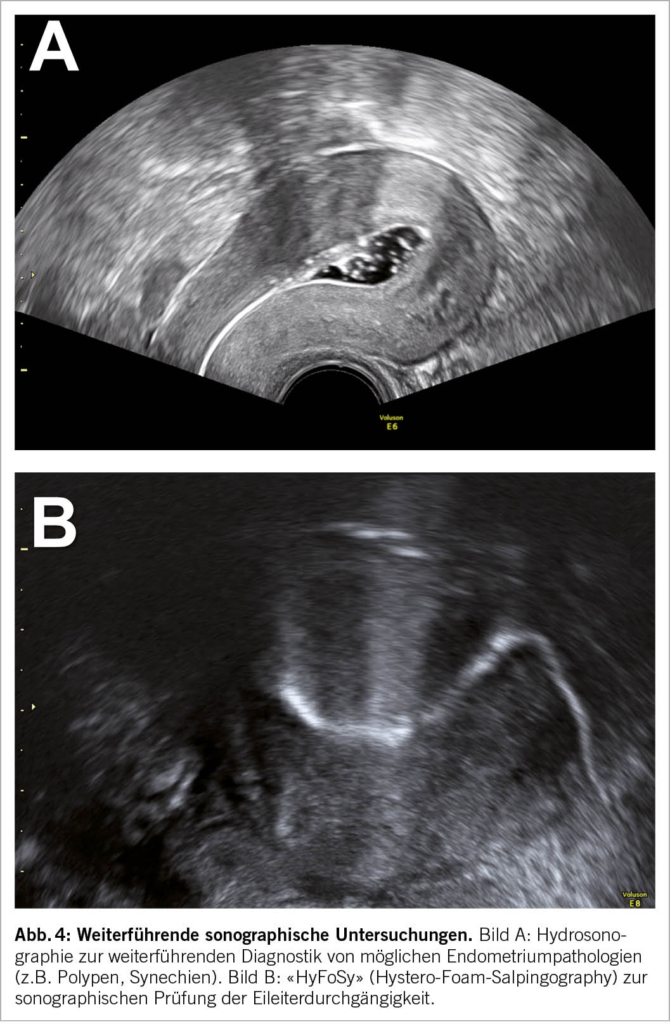

Die direkt präovulatorische Untersuchung bietet eine ausgezeichnete Gelegenheit, um möglicherweise fertilitätseinschränkende Pathologien von Uterus und Adnexen festzustellen. Die mittzyklisch erhöhten Serum-Östrogenspiegel führen zu einer gesteigerten Diffusion und Perfusion im Gewebe. Hierdurch lassen sich durch Flüssigkeit gefüllte und damit sonographisch echoleere Strukturen besser abgrenzen und beurteilen. Beispiele sind die Isthmozele (Abb. 3A) und die Hydrosalpinx (Abb. 3B). Beide Befunde können mit einer Serometra einhergehen.

Da das Endometrium durch den Östrogeneinfluss gleichmässig proliferiert sein sollte, lassen sich hier auch bestimmte Strukturveränderungen gut untersuchen. Diese beinhalten z.B. Polypen (Abb. 3C), submuköse Myome, Restmaterial einer vorangegangenen Schwangerschaft oder Konturveränderungen durch eine Adenomyose (Abb. 3D). Letztere hat in der jüngeren Vergangenheit in der Ultraschalldiagnostik und im Hinblick auf die Fertilität zunehmend an Bedeutung gewonnen. Typische sonographische Zeichen sind: Unscharf begrenzte Junktionalzone, inhomogen aufgelockertes und ggf. zystisch verändertes Myometrium, Wandasymmetrien der Gebärmutter sowie das sogenannte «fan sign» (Abb. 3D) (16).

Ein Sonderfall der Endometriumpathologien ist das Asherman-Syndrom, das sich durch folgende Auffälligkeiten im Ultraschall erkennen lässt: Mittzyklisch schmales Endometrium mit unterbrochener Junktionalzone und hyperechogenen Inseln sowie Synechien und Flüssigkeitsansammlungen (17). Besteht der Verdacht auf das Vorliegen eines Asherman-Syndroms, so kann als nächster Schritt eine Hydrosonographie sinnvoll sein (siehe Abschnitt «Weiterführende Untersuchungen»).